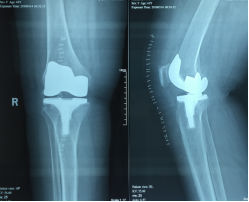

人工全膝关节置换术后X线片

人工全膝关节置换术(totalkneearthroplasty,TKA)是在上世纪 60 年代首先开始应用于临床,随着医疗水平的不断进步而日臻完善,其临床疗效也已经得到了肯定。现在膝关节假体的设计及其安装技术都有了很大的提高,人工全膝关节置换术也已经成为了比较成熟的技术。只要掌握好手术适应证(如传统保守治疗无效者、膝关节功能明显障碍并伴畸形者),做好术前准备和术后处理,均可获得满意的临床效果。